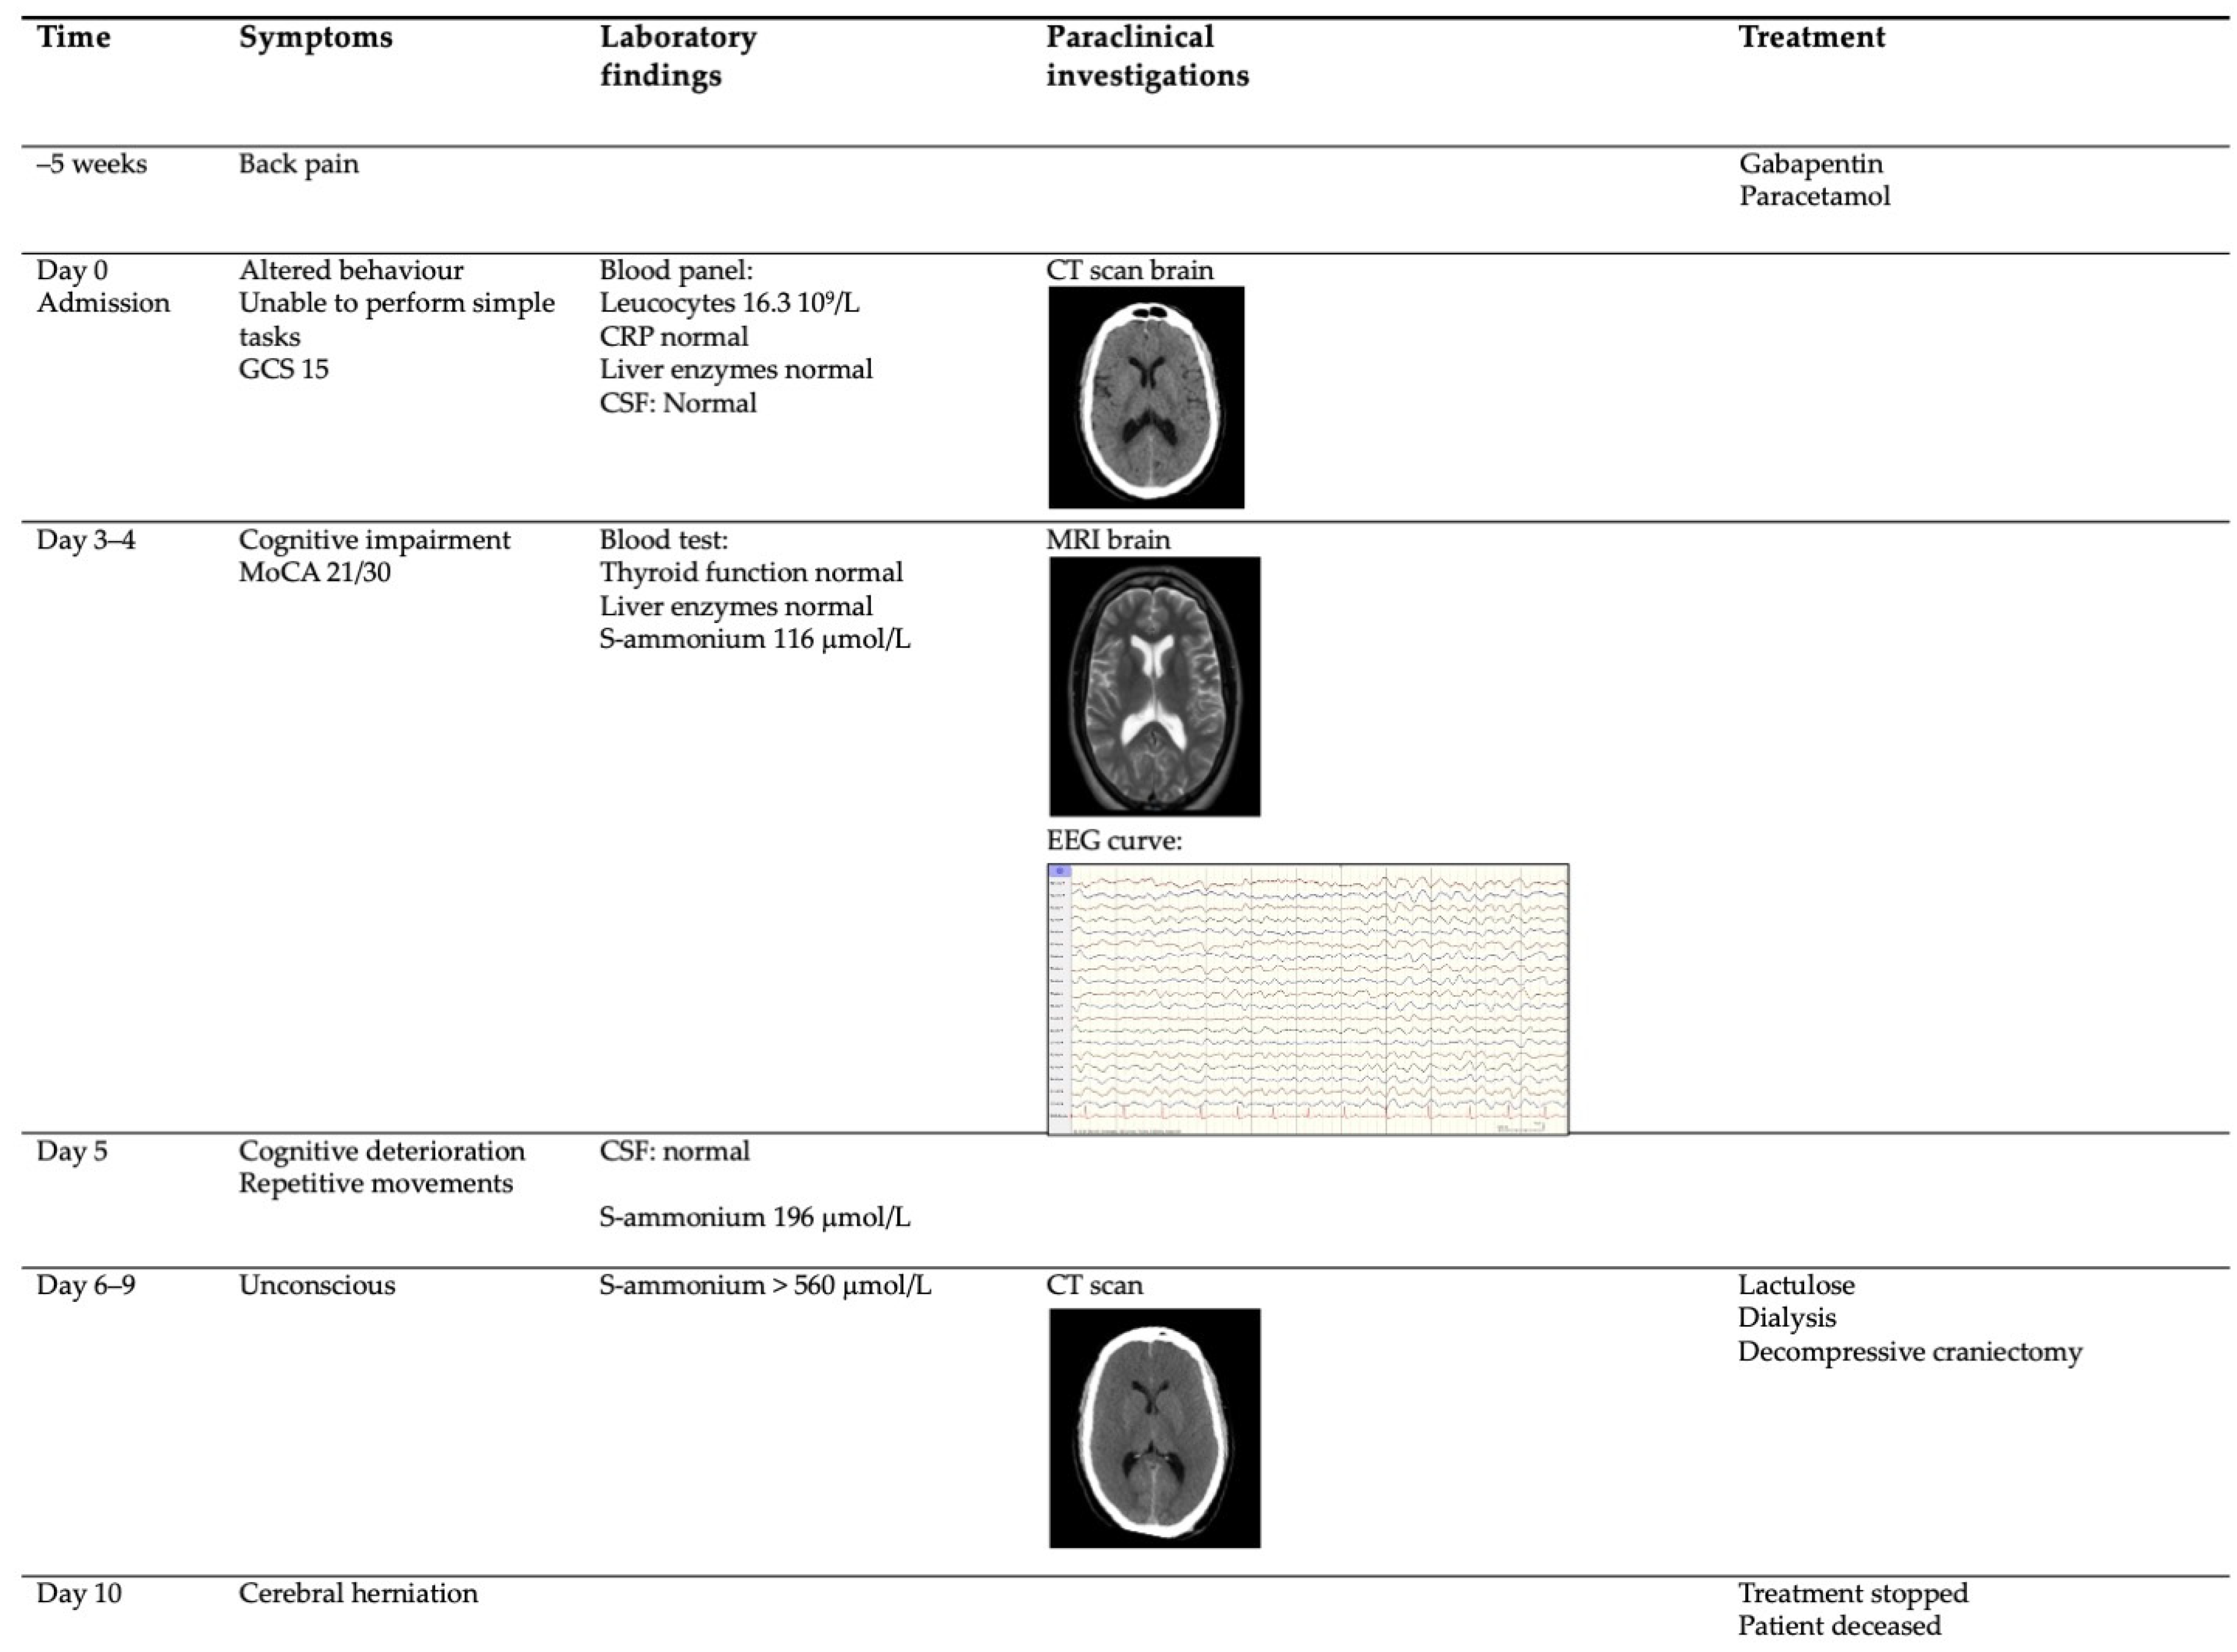

2. Case Report